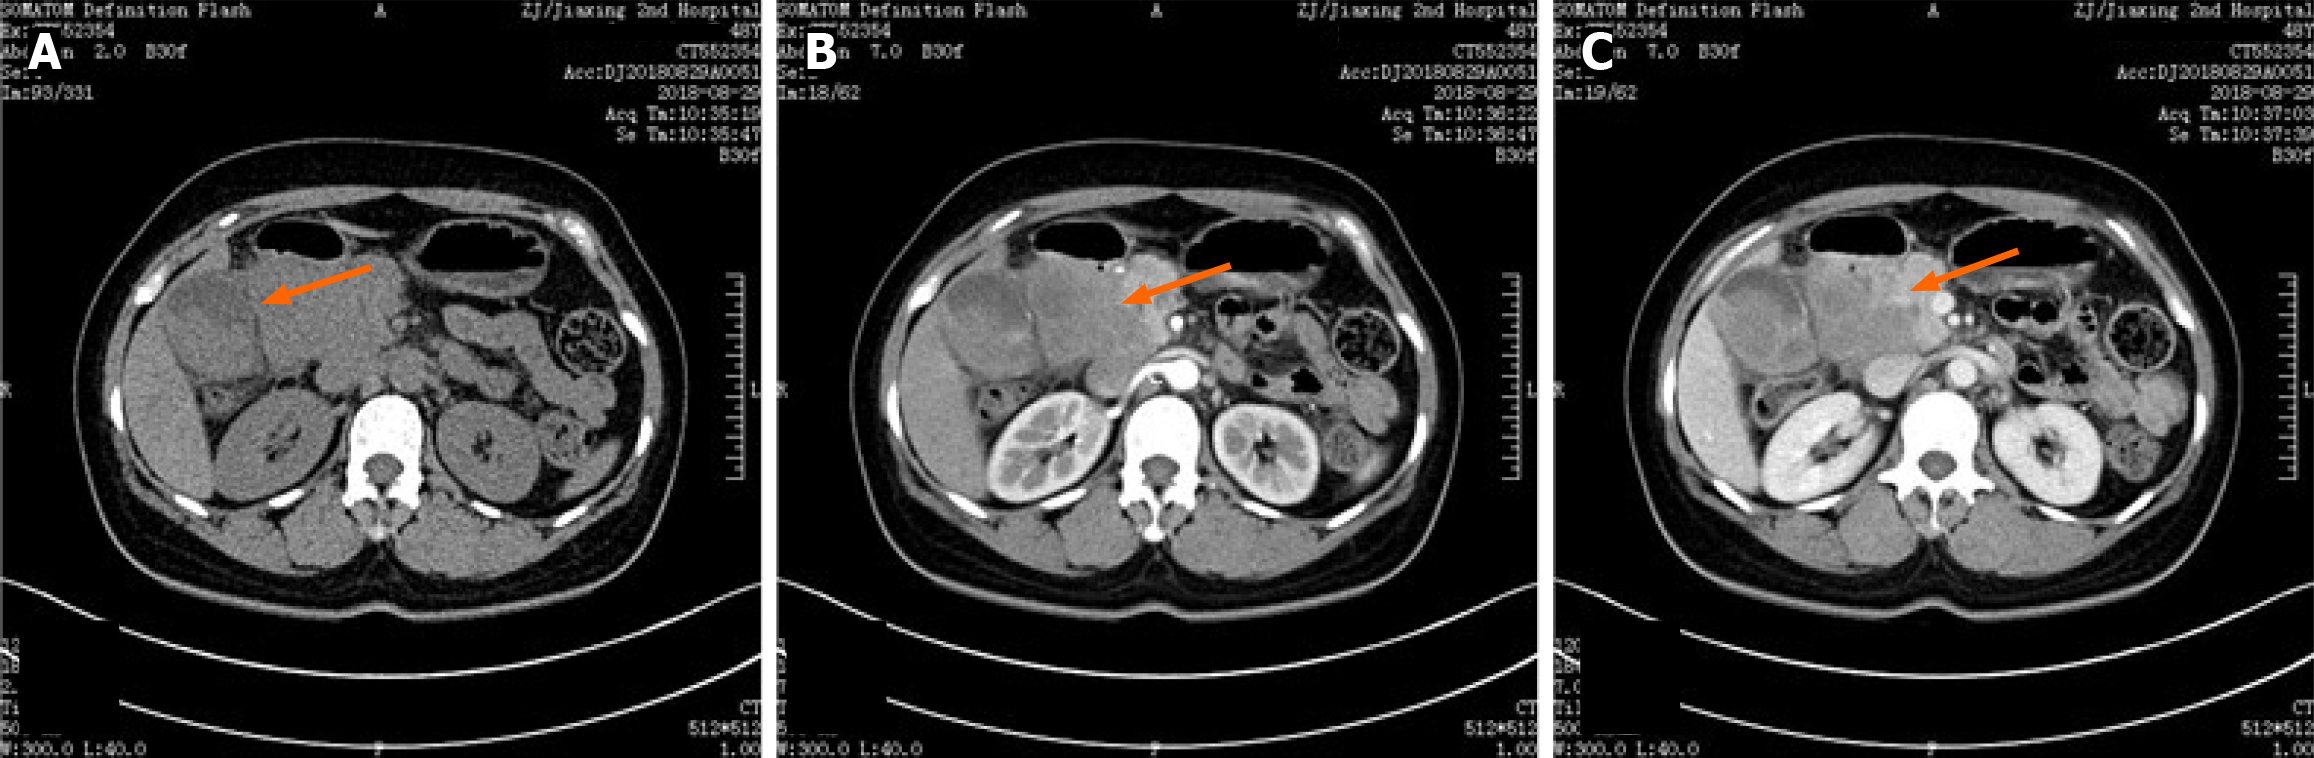

Figure 1 Abdominal computed tomography image.

A: Plain pattern; B: Arterial enhancement pattern; C: Enous enhancement pattern.